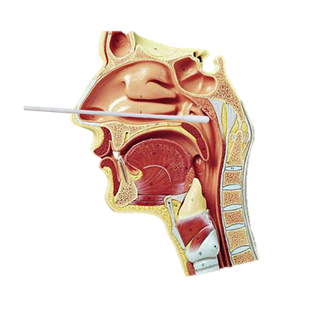

咽部示意图

那么,两者有什么不同?蔡跃新副主任医师介绍,咽部分区包括鼻咽、口咽、喉咽,三者的黏膜是连续的,均属于上呼吸道的区域,鼻咽拭子和口咽拭子只是取样的路径不一样,经口取样是口咽拭子,经鼻取样为鼻咽拭子。

鼻咽拭子